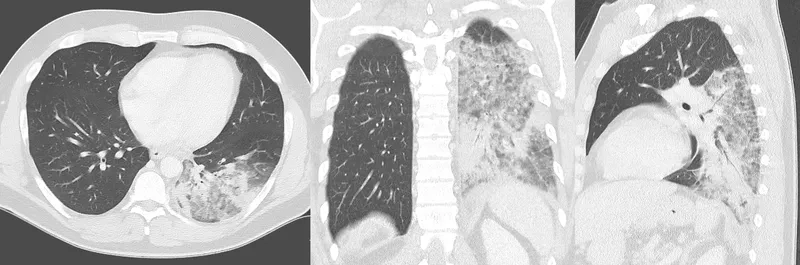

Chest X-ray showing Legionellosis pneumonia